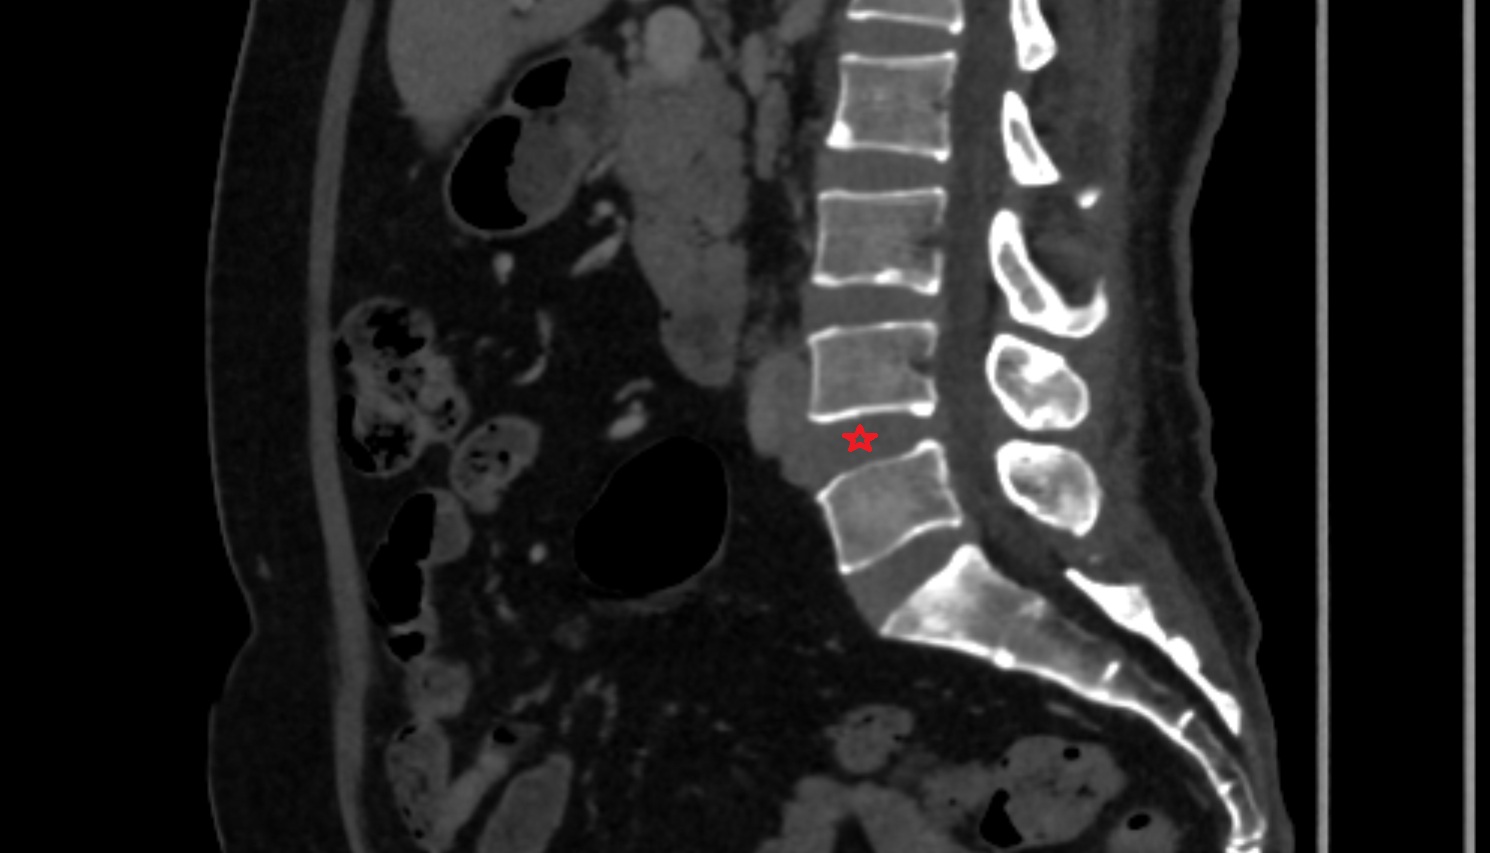

- Conus medullaris

- Cauda equina

- L5–S1 Intervertebral disc

- L4–L5 Intervertebral Disc

- L3–L4 Intervertebral Disc

- L2–L3 Intervertebral Disc

- L1–L2 Intervertebral Disc